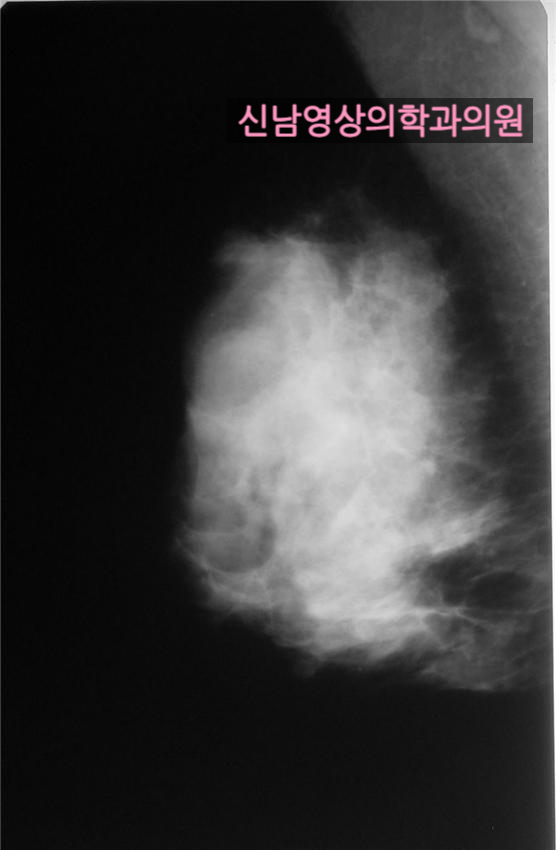

본원에서 유방 초음파를 시행한 40대 여성의 사례 |

치밀유방으로 초음파상 5.4 mm되는 종괴가 발견되었고, 조직검사상 조기암으로 진단 받아서 수술하였고,

수술 후 진단은 암 전단계인 ADH(atypical ductal hyperplasia: 비정형 유관 증식증)으로 판명 되었습니다.